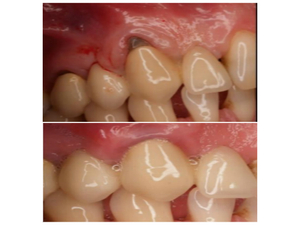

Foto de paciente atendido en Clínica Dental Sonríe

Como lo explica la Clínica Mayo, para realizar una endodoncia se suelen necesitar una o dos citas, no obstante, algunos casos pueden ser muy difíciles de tratar y el tratamiento podría extenderse. En primer lugar, el paciente asistirá a una primera cita de evaluación donde el endodoncista o dentista general realizará una radiografía dental para determinar el nivel de daño que ha sufrido el diente. Ello implica una exploración exhaustiva que permitirá evaluar si tal daño ha llegado a afectar otros dientes adyacentes y si el problema es reversible o no.

El médico podrá hacer pruebas de sensibilidad a distintas temperaturas y podrá recetar al paciente un tratamiento con antibióticos para eliminar la infección antes de iniciar con el procedimiento de endodoncia. Durante la primera cita, el médico también explicará al paciente todos los detalles sobre su padecimiento y recomendará el tratamiento más indicado.

En consecuencia, si se llegase a tratar de una endodoncia, el médico explicaría todo el proceso, los resultados que se obtendrán y por supuesto, los cuidados que deben tenerse con el objetivo de no estropear el trabajo realizado. Cabe destacar que dependiendo de cada caso y su urgencia, el médico podrá iniciar el tratamiento el mismo día o bien agendar una segunda cita.